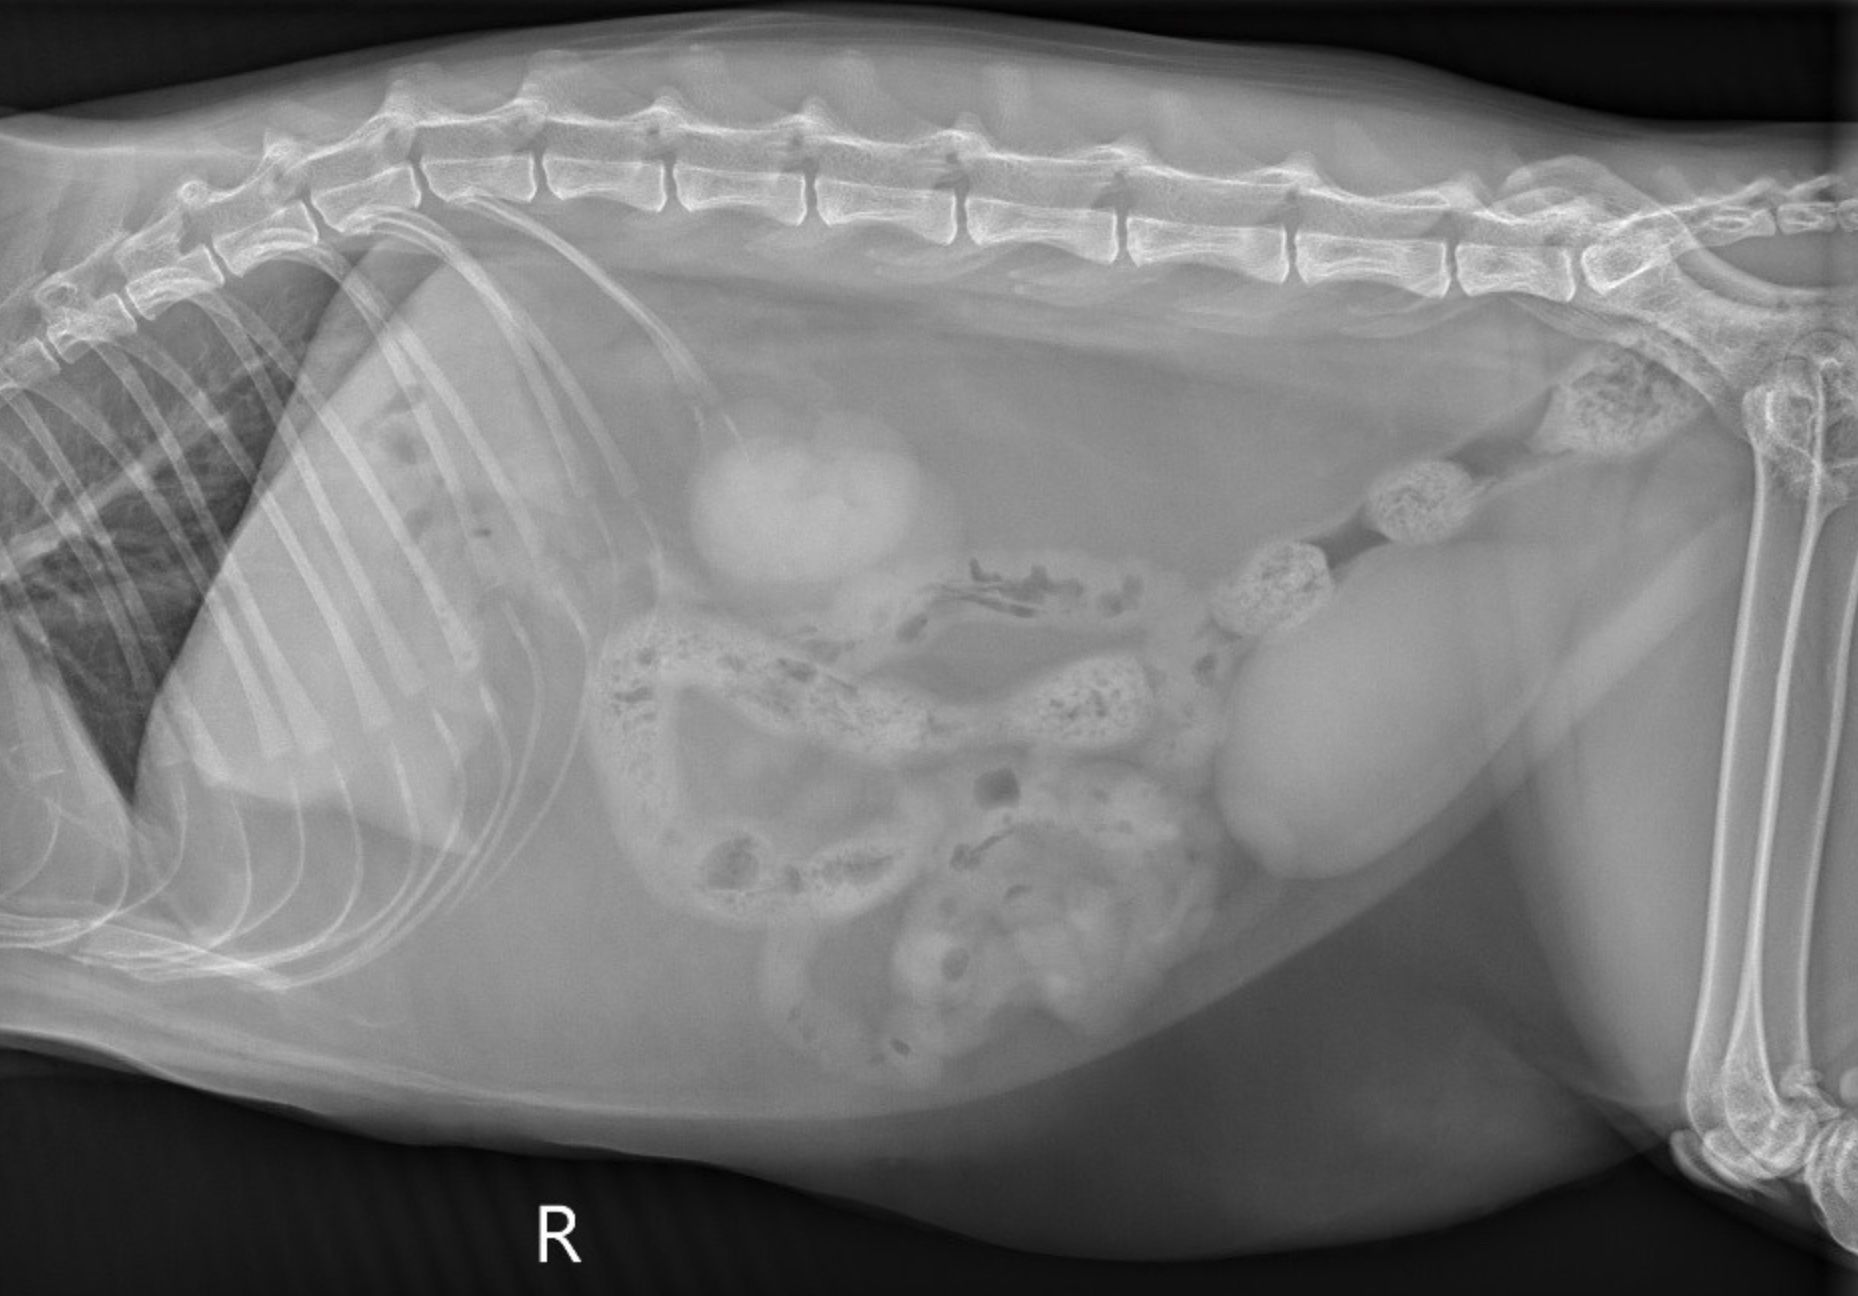

Initial diagnostics in a vomiting animal should include abdominal imaging. Three-view abdominal radiographs and ultrasound are the most common forms of imaging.

When evaluating abdominal radiographs, 2 populations of bowel are characteristic for a mechanical obstruction. Historically, in dogs, a ratio greater than 1.6 comparing the diameter of small intestine to the height of L5 vertebra has been recommended to determine presence of obstruction.1 In cats, this has been reported as a ratio greater than 3.0 when comparing the diameter of small intestine to height of the cranial end plate of L2 vertebra.2 However, more recent findings in literature have shown that objective ratios don’t provide more accuracy than subjective evaluation.3